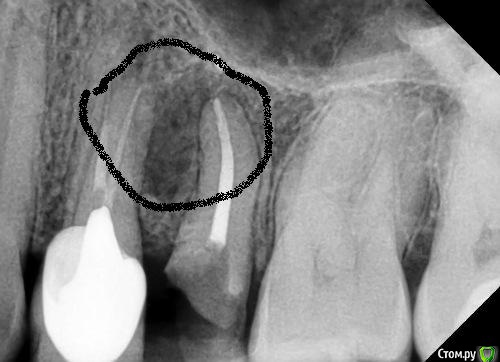

vse32 Опубликовано 22 декабря, 2017 Поделиться Опубликовано 22 декабря, 2017 имхо, причинный 2.4 Смотрите внимательнее контур кисты. Он же как нимб вокруг 25. Ссылка на комментарий

red_butler Опубликовано 22 декабря, 2017 Поделиться Опубликовано 22 декабря, 2017 Смотрите внимательнее контур кисты. Он же как нимб вокруг 25. У 2.5 сохранена периодонтальная щель, у 2.4 нет Ссылка на комментарий

vse32 Опубликовано 22 декабря, 2017 Поделиться Опубликовано 22 декабря, 2017 У 2.5 сохранена периодонтальная щель, у 2.4 нет Если не затруднит, нарисуйте как видите контур кисты.Если проблемный 24, то там может и эндодонтии хватит. Каналы не "айс". Ссылка на комментарий

vse32 Опубликовано 22 декабря, 2017 Поделиться Опубликовано 22 декабря, 2017 свищ, кстати примерно тут. Ссылка на комментарий

red_butler Опубликовано 22 декабря, 2017 Поделиться Опубликовано 22 декабря, 2017 Если не затруднит, нарисуйте как видите контур кисты.Если проблемный 24, то там может и эндодонтии хватит. Каналы не "айс". 2 Ссылка на комментарий

shishok Опубликовано 22 декабря, 2017 Поделиться Опубликовано 22 декабря, 2017 свищ, кстати примерно тут. А с гуттой снимок не делали? Ссылка на комментарий